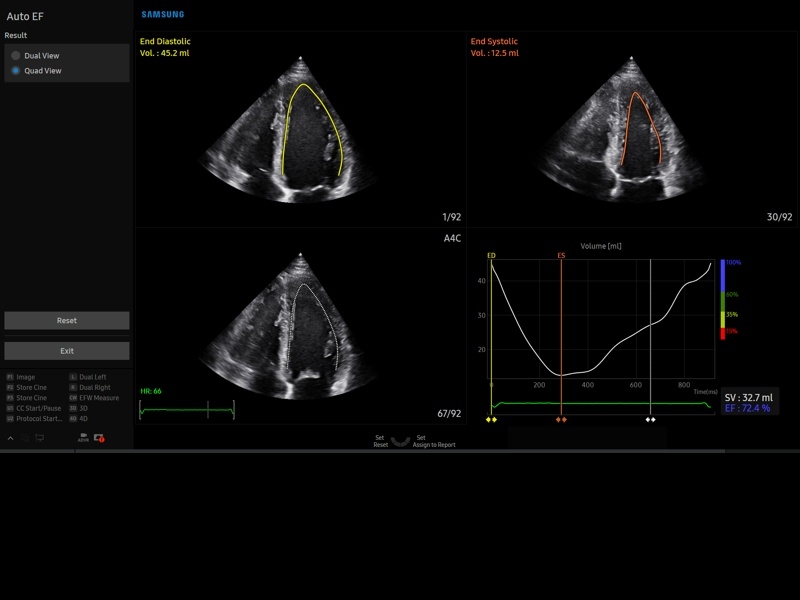

• Пакет кардиологических исследований.

М-режим:измерение диаметра аорты, передне-заднего размера ЛП, толщины МЖП (систолическая и диастолическая), толщины ЗСЛЖ (систолическая и диастолическая), размеров ЛЖ и ПЖ (систолический и диастолический), ФВ (Teichholz).

B-режим:измерение диаметра аорты (восходящей, дуги, нисходящей, на уровне синусов Вальсальвы, на уровне створок аортального клапана), определение размеров ЛП и ПП (максимальный, минимальный, систолический, диастолический, переднее-задний, верхнее-нижний, медиально-латеральный), расчет объемов ЛП и ПП, объемов ЛЖ (метод "Площадь-Длина", метод дисков (Simpson)), массы миокарда ЛЖ, индекса массы миокарда ЛЖ.

CD-режим (ЦДК):измерение радиуса ПФСМР (PISA), полуколичественная оценка трансмитрального, транстрикуспидального, трансаортального и транспульмонального кровотока (оценка регургитации), оценка аномальных сбросов крови через МПП И МЖП.

PW-режим (импульсно-волновой допплер):автоматическая, полуавтоматическая и ручная трассировка допплеровского спектра митрального, аортального и трикуспидального клапанов, клапана легочной артерии, кровотока в выходном тракте ЛЖ и ПЖ (пиковая/средняя скорость, пиковый/средний градиент давления, время изоволюметрического расслабления ЛЖ, время ускорения, замедления, выброса), оценка кровотока легочных и печеночных вен.

CW-режим (постоянно-волновой допплер):программы расчета работы митрального, аортального и трикуспидального клапанов, клапана легочной артерии.

TD-режим (тканевой допплер):количественная оценка локальной сократительной функции стенок ЛЖ и ПЖ.

Сокращения:ЛП/ПП - левое/правое предсердие, МЖП - межжелудочковая перегородка, МПП - межпредсердная перегородка, ЗСЛЖ - задняя стенка левого желудочка, ЛЖ/ПЖ - левый/правый желудочек, ФВ - фракция выброса, ПФСМР - площадь формирующейся струи митральной регуритации (PISA - proximal isovelocity surface area), ПСС/КДС - пиковая систолическая / конечная диастолическая скорость.